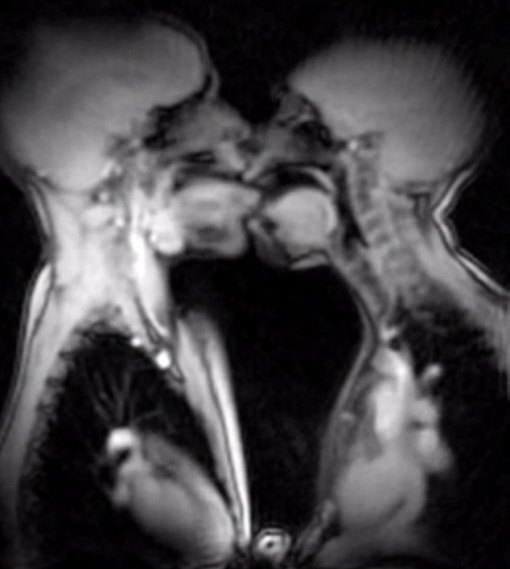

Magneettikuvaus (MRI) on erinomainen tapa diagnosoida sairauksia. Magneetti-impulssit ovat röntgensäteistä poiketen ihmiselle täysin harmittomia, ja näiden avulla on mahdollista nähdä erittäin tarkasti myös pehmeän kudoksen muodostumat ja verenkierto. Magneettikuvauksen turvallisuus ja monipuoliset mahdollisuudet ovat inspiroineet Berliinissä toimivaa Charité -yliopistosairaalaa koettelemaan magneettikuvauksen rajoja. Oheisella videolla on mahdollista nähdä esimerkiksi synnytys, seksiä ja muita ihmiskehon toimintoja magneettikuvattuna. Katso ja äimisty!